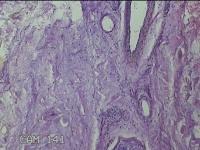

骶尾部包块

性别

男

年龄

37岁

临床诊断

骶良性肿瘤

一般病史

发现骶尾部包块10年余。

标本名称

大体所见

灰白粉红色组织3.5x1.3x1cm一块,表面带梭形皮肤3.5x1.3cm皮下见包块3x1.3cn一个,切开包块呈实性,切面灰白粉红色,质中。

图2